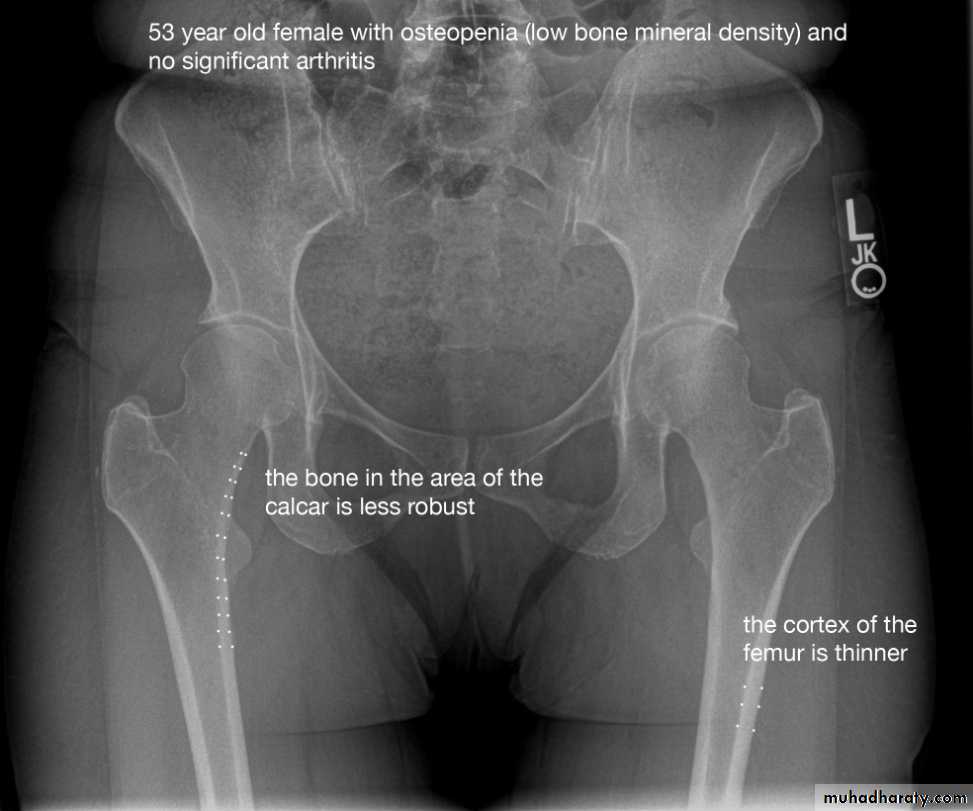

1.decrease in bone density , it can be focal or generalized

5. alteration in trabecular pattern